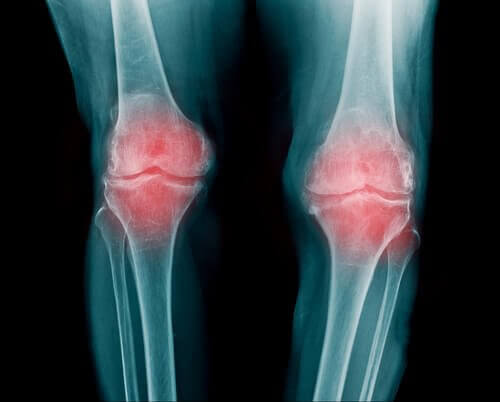

Ревматоиден артрит

- Ревматоидният артрит е възпаление на ставата. То може да повлияе на множество различни стави. По принцип засяга пръстите, ръцете и коленете.

- Хората, страдащи от ревматоиден артрит, имат намалена подвижност. След изтръпването се появява още по-остра болка.

- То се появява при натрупване на калциеви отлагания в ставата. Тогава възниква изтръпването на ставите и отслабването на хрущяла, който се разрушава постепенно и води до влошаване на болката.

- Наблюдава се най-често в китките, пръстите и коленете, макар че може да засегне и други стави. Това заболяване е свързано с остеоартрита и нарушенията на щитовидната жлеза.